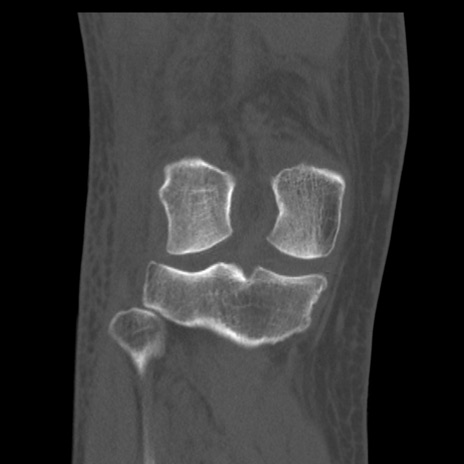

右膝関節CT

矢状断像